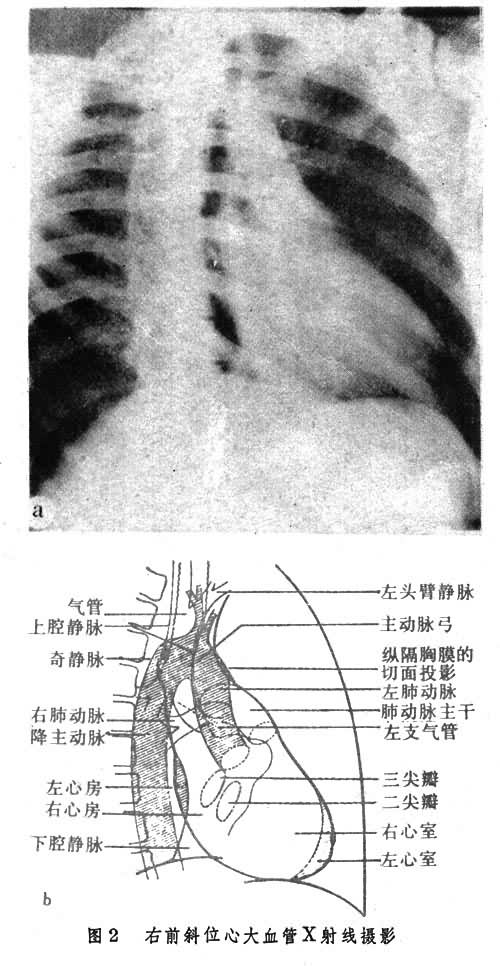

(2)右前斜位(RAO),身体右侧前斜45°(图2)。心前缘由三段弧组成上段为升主动脉弓部前缘,中段为肺动脉干及右心室圆锥部,下段主要为右心室及下端左心室构成。后缘上段由上腔静脉、升主动脉后缘构成,其界线不清楚。下段主要为左心房,下段之下端为右心房和下腔静脉,后者部分与横膈重叠。降主动脉位于心影后缘与脊椎之间。